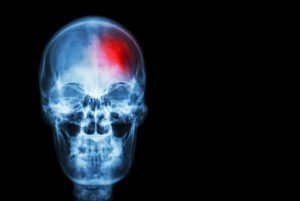

Schädel-Hirn-Verletzungen erhöhen das Risiko für schwere Folgeerkrankungen22. Juni 2022 Foto: © stockdevil, stock.adobe.com Eine große prospektive Kohortenstudie aus den USA zeigte erstmals, dass nach Schädel-Hirn-Traumata das Risiko für schwere Folgeerkrankungen im Studienzeitraum von zehn Jahren signifikant zunahm. Dies betraf chronische kardiovaskuläre, psychiatrische und endokrine Erkrankungen – so verdoppelte sich beispielsweise das Risiko für Schlaganfälle, Bluthochdruck, Demenz und Diabetes mellitus. Das Risiko für Folgeerkrankungen war in allen Altersgruppen höher als bei altersentsprechenden Kontrollpersonen – dies galt auch für jüngere Patientinnen und Patienten im Alter zwischen 18 und 40 Jahren. Eine prospektive longitudinale Kohortenstudie aus Boston untersuchte prospektiv potenzielle Langzeitfolgen von Schädel-Hirn-Traumata (SHT) bei zuvor gesunden Menschen. Man nutzte dazu Registerdaten eines akademischen medizinischen Zentrums („MGB Research Patient Data Registry“/RPDR) und konnte so im Gegensatz zu früheren Untersuchungen Personen mit präexistenten Komorbiditäten von der Analyse ausschließen. Patientinnen und Patienten ab 18 Jahren, die ein leichtes oder moderates bis schweres SHT erlitten hatten, wurden über zehn Jahre prospektiv nachbeobachtet. Dabei wurden die Inzidenzen von 21 Erkrankungen in vier Organsystemen ermittelt und mit Kontrollen verglichen. Dazu gehörten kardiovaskuläre Erkrankungen bzw. Risikofaktoren (z. B. Bluthochdruck, Hyperlipidämie, Adipositas, koronare Herzerkrankung), endokrine Störungen (z. B. Diabetes mellitus, Schilddrüsen-, Hypophysen- und Nebennierenfunktion, erektile Dysfunktion), neurologische Erkrankungen (z. B. Schlaganfall, Krampfanfälle, Demenzen) sowie psychiatrische Erkrankungen (z. B. Depressionen, Psychosen, Angst- und Schlafstörungen, Suizidalität, Substanzmissbrauch, z. B. von Schmerzmitteln/Opioiden, Alkohol). Zu Vergleichszwecken wurden aus dem Register Kontrollpersonen, die kein SHT erlitten hatten, herangezogen und nach Alter, Geschlecht und anderen Merkmalen mit den SHT-Betroffenen gematcht. Die Erkrankungen waren nach den internationalen Klassifikationen ICD-9 oder ICD-10 definiert.Insgesamt konnten in drei Gruppen je 4.351 Personen eingeschlossen und analysiert werden: Betroffene mit leichtem SHT (medianes Alter 45 Jahre), mit mittlerem bis schwerem SHT (medianes Alter 47 Jahre) und nicht-exponierte Kontrollen (medianes Alter 46 Jahre). In jeder Gruppe waren ca. 45% der Teilnehmenden weiblich. Patientinnen und Patienten beider SHT-Gruppen hatten gegenüber der Kontrollgruppe ein signifikant höheres Risiko für kardiovaskuläre, endokrine, neurologische und psychiatrische Erkrankungen. So war das Hypertonie-Risiko mehr als doppelt so hoch (leichtes SHT: hazard ratio HR 2,5 und moderat/schweres SHT: HR 2,4), das Diabetesrisiko war in beiden SHT-Gruppen ebenfalls fast verdoppelt (HR jeweils 1,9), das Schlaganfallrisiko nahm signifikant zu (HR 2,2 bei leichtem SHT und HR 3,6 bei moderat/schwerem SHT) und das Demenz-Risiko vervierfachte sich (HR 3,8 bei leichtem SHT und HR 4,2 bei moderat/schwerem SHT).Patientinnen und Patienten mit moderatem bis schweren SHT hatten sogar ein gegenüber der Kontrollgruppe signifikant höheres 10-Jahres-Mortalitätsrisiko: In dieser Gruppe verstarben 432 Personen (9,9%) gegenüber 250 Todesfällen (5,7%) in der Kontrollgruppe (p ≤ 0,001). Dabei waren Hypertonie und Diabetes (je HR 1,3), koronare Herzerkrankung (HR 2,2) und Nebennieren-Insuffizienz (HR 6,2) mit einer höheren Mortalität assoziiert.Nach Ansicht des Autorenteams sind die möglichen Erklärungen für die Zunahme der Risiken und beschriebenen Folgeerkrankungen nach einem SHT sehr komplex. So könnten veränderte Verhaltensgewohnheiten bzw. Lifestyle-Faktoren eine Rolle spielen, wie z. B. eine reduzierte körperliche Aktivität, ungesunde Ernährung, Schlafstörungen, regelmäßige Schmerzmitteleinnahme oder vermehrter Alkoholkonsum. Denkbar sind auch Einflüsse entzündlicher und immunologischer Prozesse bis hin zu einer veränderten Darmflora (z. B. nach Klinikaufenthalt oder durch Medikamente).„Die wesentliche neue Erkenntnis der Studie ist, dass zuvor gesunde Erwachsene nach einem Schädel-Hirn-Trauma, egal welchen Schweregrades, auch ein erhöhtes Risiko für kardiovaskuläre und endokrine Folgeerkrankungen zu haben scheinen, und das in allen Altersgruppen. Bisher war nur bekannt, dass nach einem SHT das Risiko für neurologische und psychiatrische Erkrankungen steigt“, kommentiert Prof. Dr. Hans-Christoph Diener, Essen, Pressesprecher der DGN.Prof. Dr. Peter Berlit, DGN-Generalsekretär verweist auf die Limitationen dieser Studie. So handle es sich um eine reine Assoziationsstudie. Verzerrungs- und Störfaktoren wie beispielsweise untererfasste präexistente psychiatrische Erkrankungen seien gerade bei monozentrischen Daten nicht sicher auszuschließen. Der sozioökonomische Status beispielsweise wurde gar nicht berücksichtigt. „Dennoch liefert die Studie Signale, die ernst genommen werden müssen. Menschen mit Schädel-Hirn-Trauma sollten um diese Risiken wissen und konsequent auf eine gesunde Lebensweise zu achten, um das persönliche Diabetes-, Bluthochdruck- und Schlaganfallrisiko zu senken“ betont Berlit. „Auch sollten sie sich alle zwei Jahre hausärztlich untersuchen lassen, um zunächst symptomlose Erkrankungen wie Bluthochdruck und Diabetes frühzeitig zu erkennen und zu behandeln.“